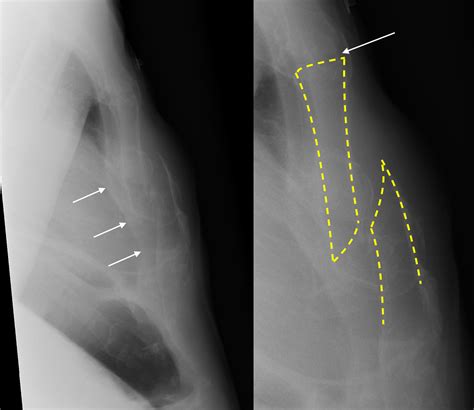

Interpreting the results of a sternum X ray requires the expertise of a radiologist. The images are reviewed for various abnormalities, including:

• Fractures: Visible breaks or cracks in the sternum.

• Infections: Signs of bone destruction or inflammation.

• Tumors: Abnormal growths or masses within the bone.

• Dislocations: Misalignment of the sternum or adjacent structures.

If any abnormalities are detected, further diagnostic tests or treatments may be recommended based on the findings.

Common Findings in a Sternum X Ray

Several common findings can be identified through a sternum X ray. These include:

• Normal Anatomy: A clear view of the sternum and surrounding structures without any abnormalities.

• Fractures: Visible breaks in the bone, which may appear as lines or gaps.

• Osteomyelitis: Signs of infection, such as bone destruction or inflammation.

These findings help healthcare providers determine the appropriate course of treatment.